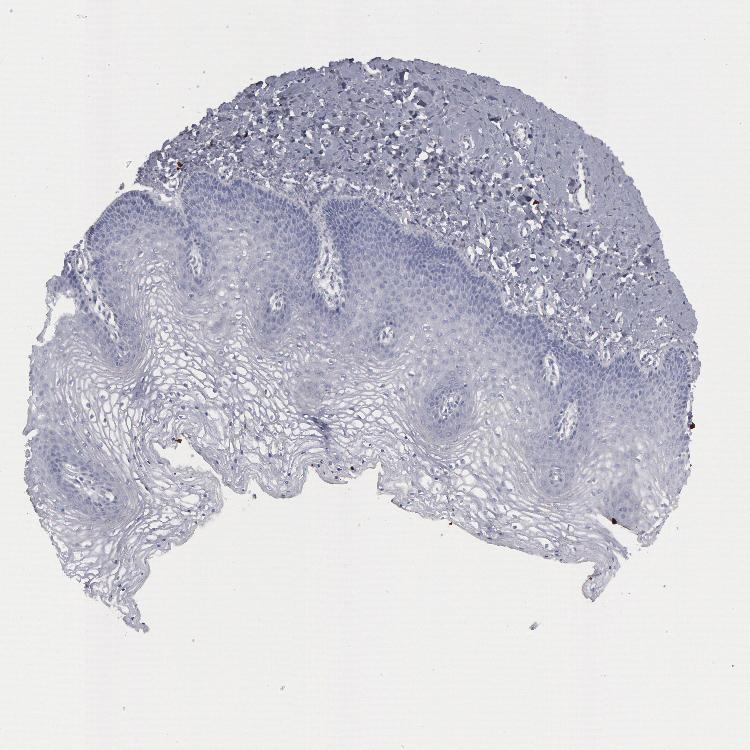

VAGINA - Antibody stainingi

Antibody staining in the annotated cell types in the current human tissue is reported as not detected, low, medium, or high, based on conventional immunohistochemistry profiling in selected tissues. This score is based on the combination of the staining intensity and fraction of stained cells.

Each image is clickable and will lead to virtual microscopy that enables deeper exploration of all samples and also displays staining intensity scores, fraction scores and subcellular localization as well as patient and tissue information for each sample.

Antibody HPA001040Antibody HPA001391Antibody CAB020817

Squamous epithelial cells Not detectedNot detectedNot detected